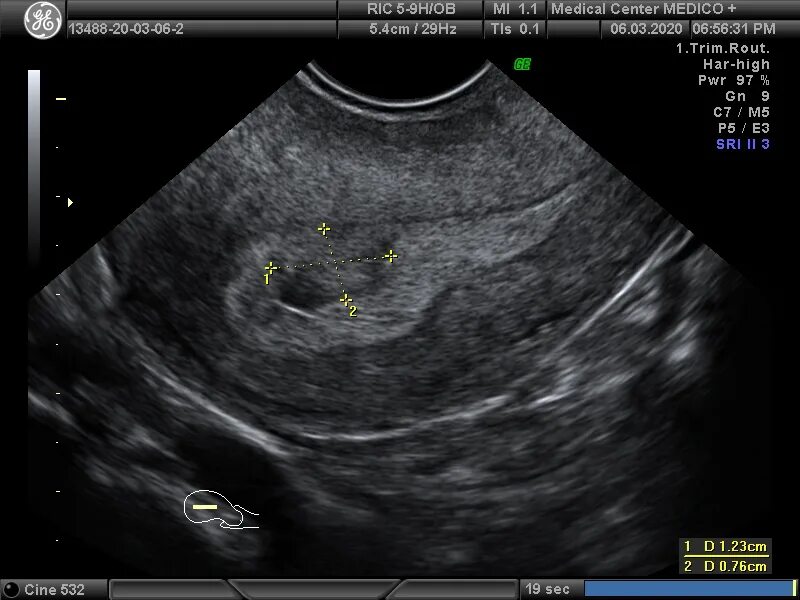

Узел в матке тип 4